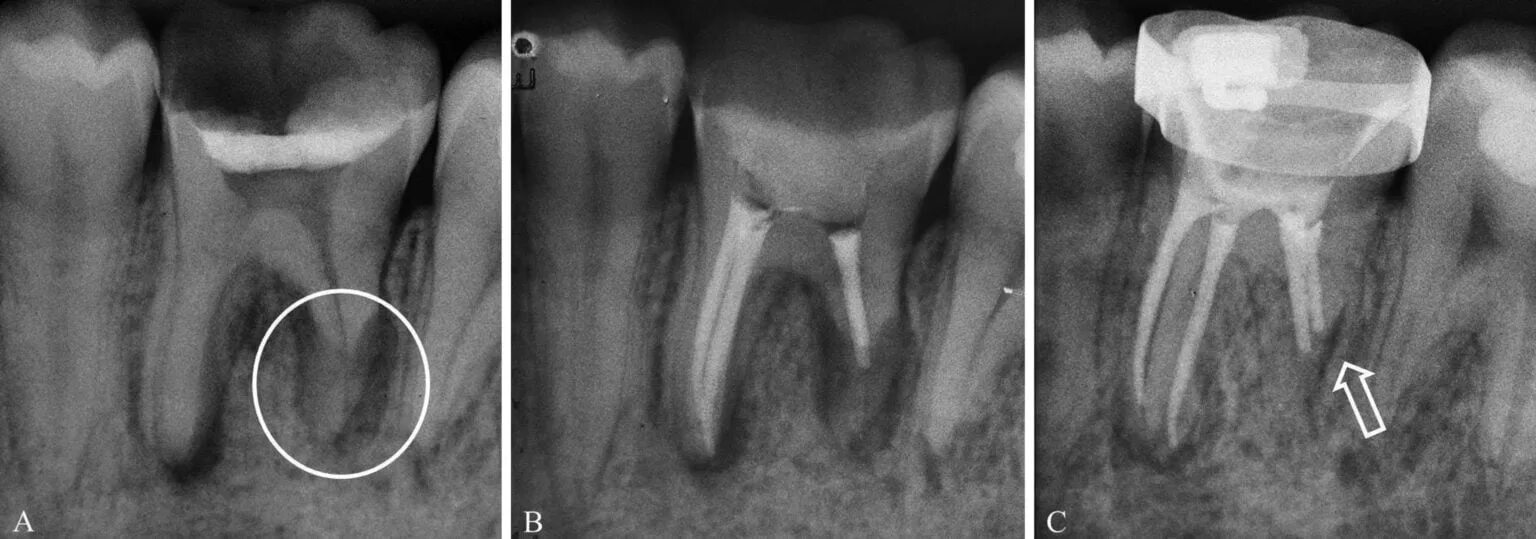

Признаки резорбции